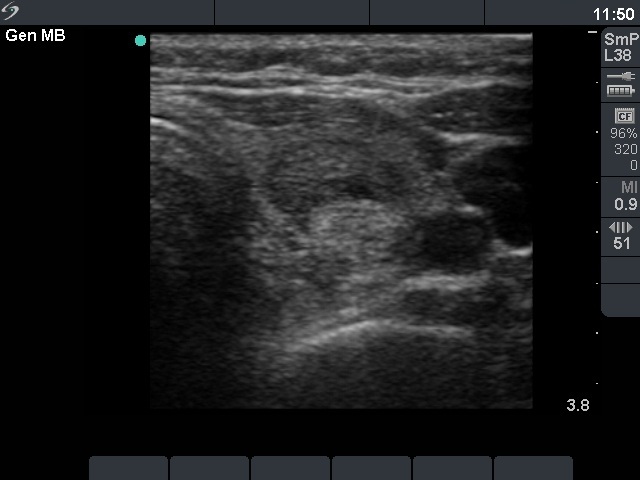

Ultrasonography: the thyroids were echonormal and contained multiple small hypoechogenic lesions. There was a mixed moderately hypoechogenic-echonormal nodule in the left lobe. The nodule exhibited a halo sign and peri- and intranodular blood flow.